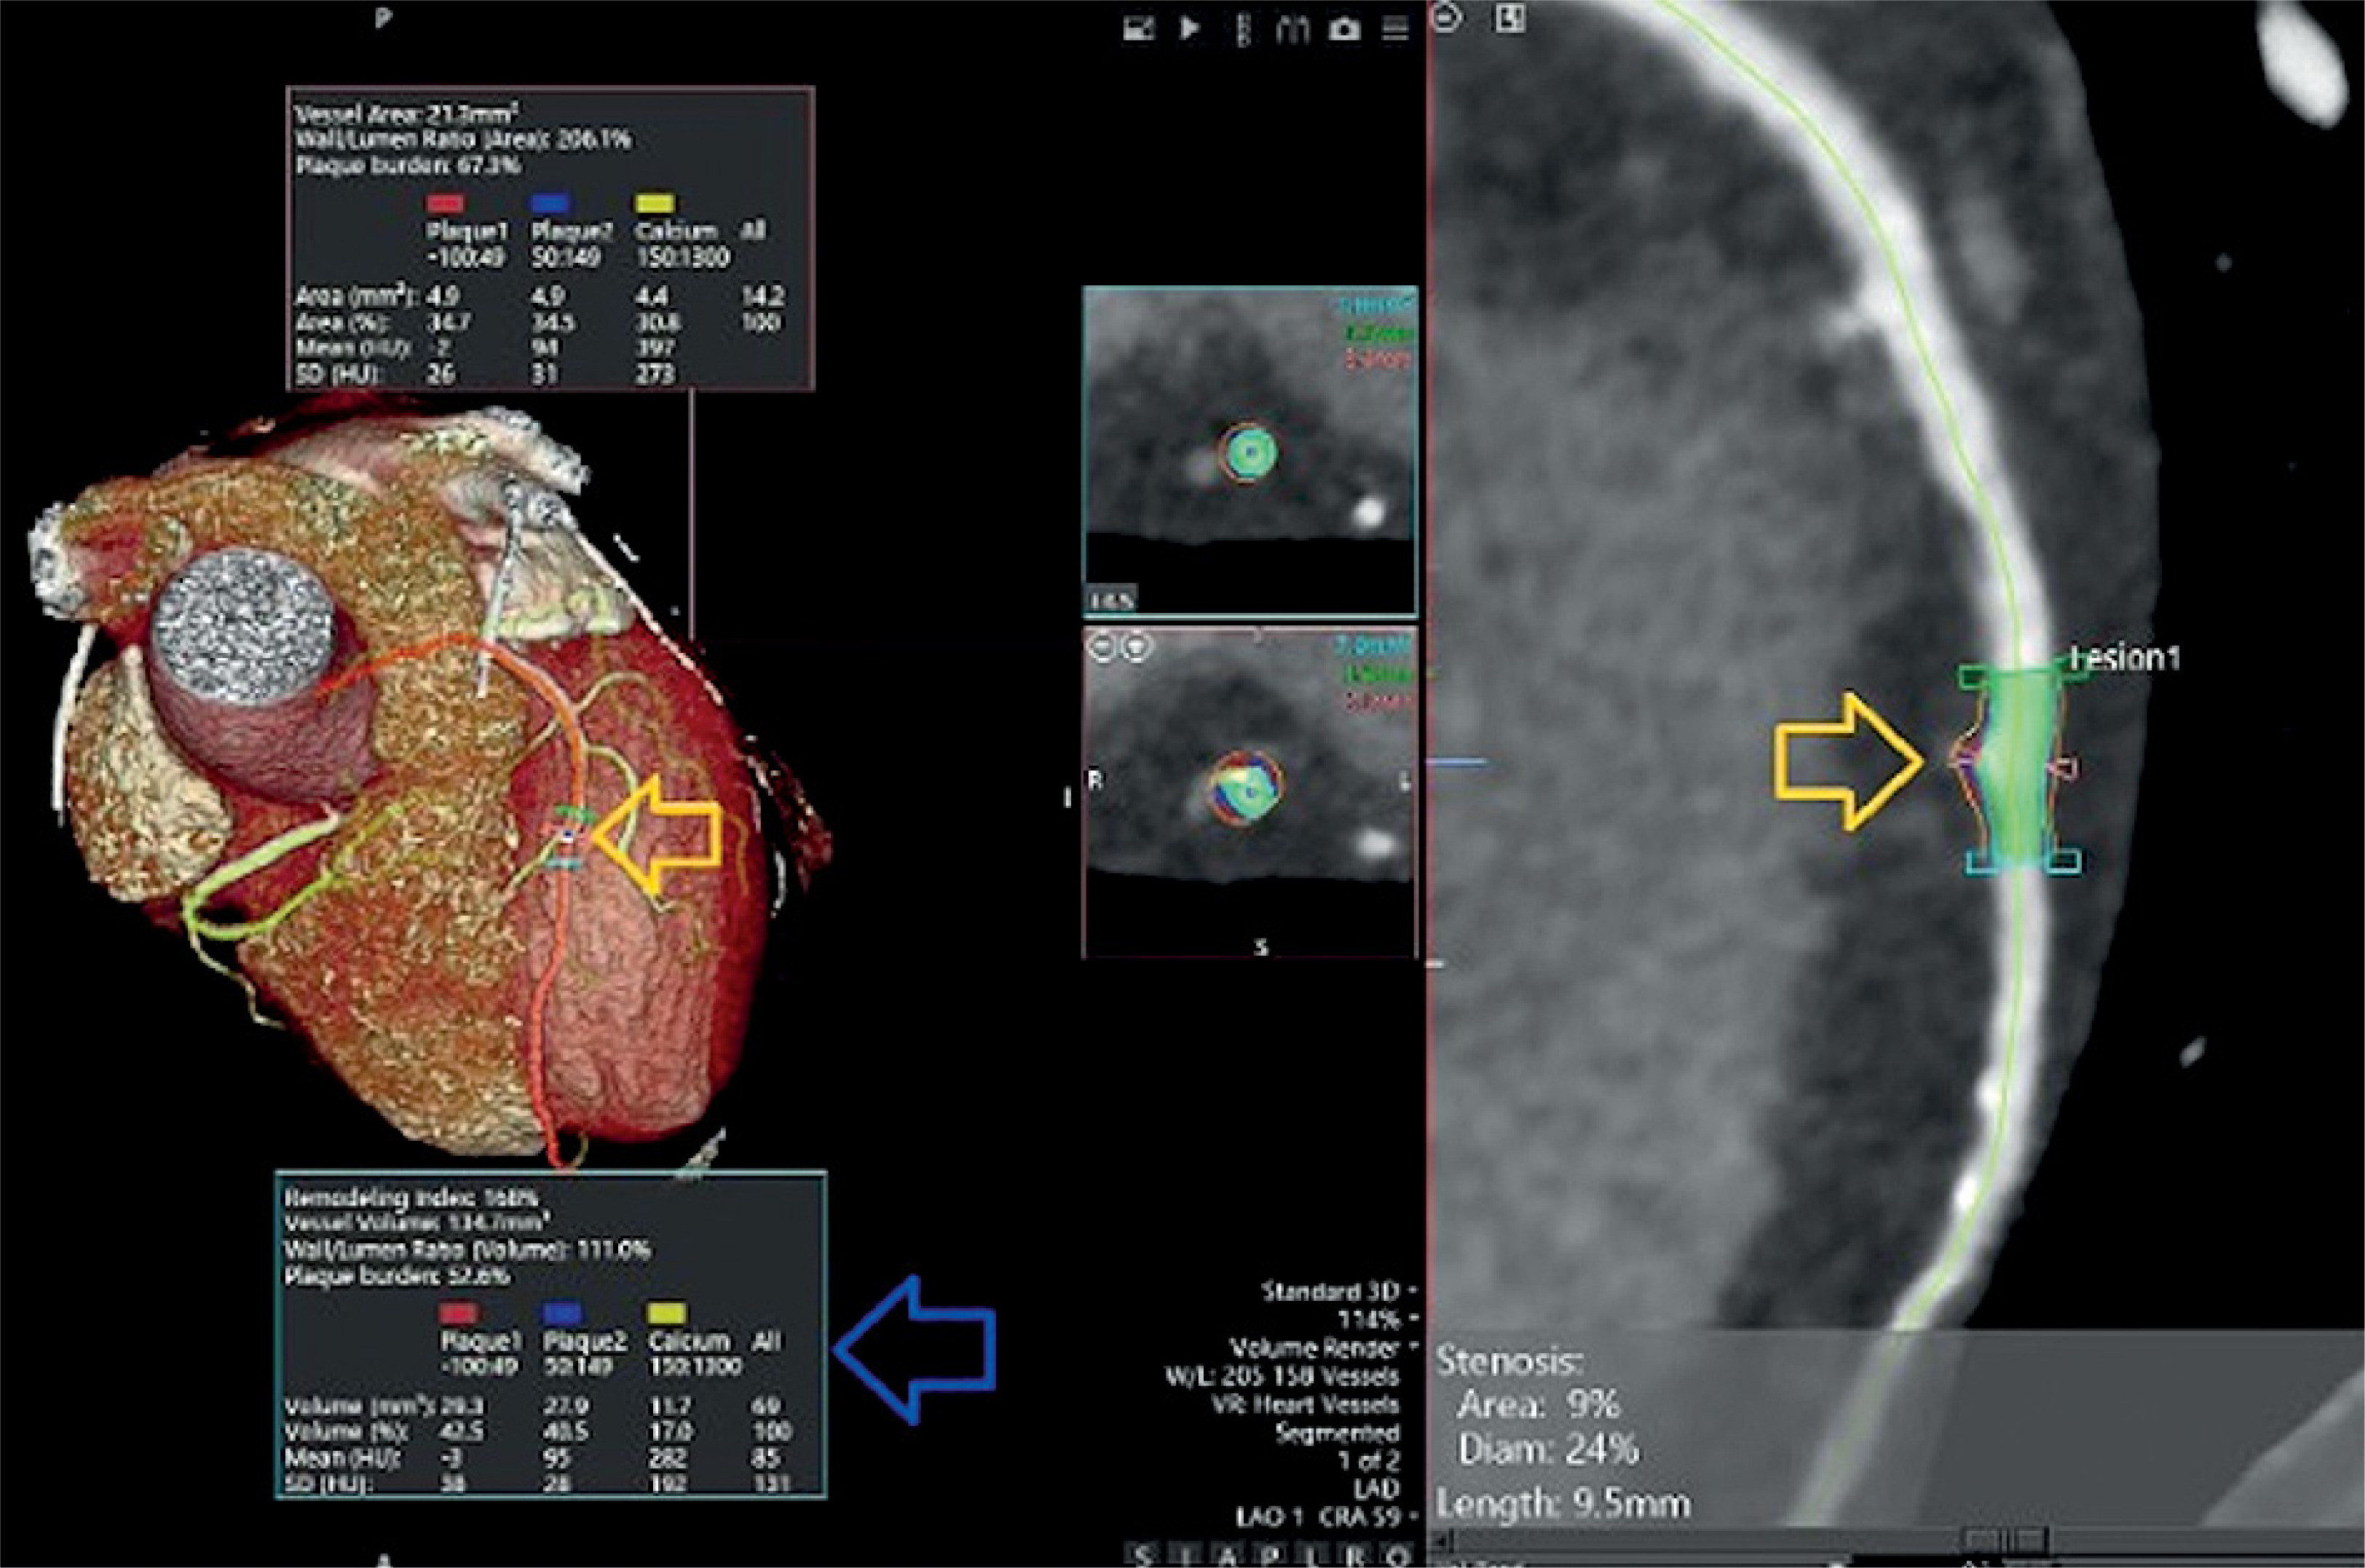

Figure 1

Three-dimensional (3D) volume-rendered and quantitative plaque analysis images of the patient’s coronary arteries obtained by multidetector computed tomography angiography (MDCTA). The yellow arrows indicate the lesion showing positive remodeling in the left anterior descending (LAD) artery and its narrowest cross-section. The blue arrows point to the cross-sectional (upper box) and volumetric (lower box) quantitative plaque analysis results (plaque burden, plaque composition, etc.) for this lesion. Plaque 1 – low-density, non-calcified (soft); plaque 2 – non-calcified (mixed); plaque 3 – calcified